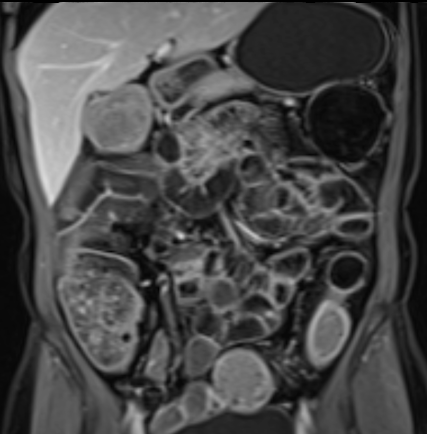

Phát hiện hẹp lòng ruột ở đại tràng sigma, không thể vượt qua được khi nội soi.

MR-enterography được thực hiện để đánh giá mức độ lan rộng của chỗ hẹp.

Ruột non bình thường, nhưng ghi nhận các đoạn hẹp ở đại tràng xuống và đại tràng ngang.

Cả hai đoạn hẹp đều có thành ruột dày đến 8 mm và ngấm thuốc rõ rệt theo kiểu niêm mạc ở đại tràng xuống và kiểu phân lớp ở đại tràng ngang.

Giãn ruột trước chỗ hẹp được ghi nhận ở cả hai đoạn.

Do các chỗ hẹp này không hiện diện khi nội soi đại tràng trước khi điều trị kháng TNF, nhiều khả năng chúng đã hình thành trong quá trình điều trị.

Do đó, quyết định phẫu thuật cắt đại tràng gần toàn bộ với miệng nối hồi-sigma đã được đưa ra.